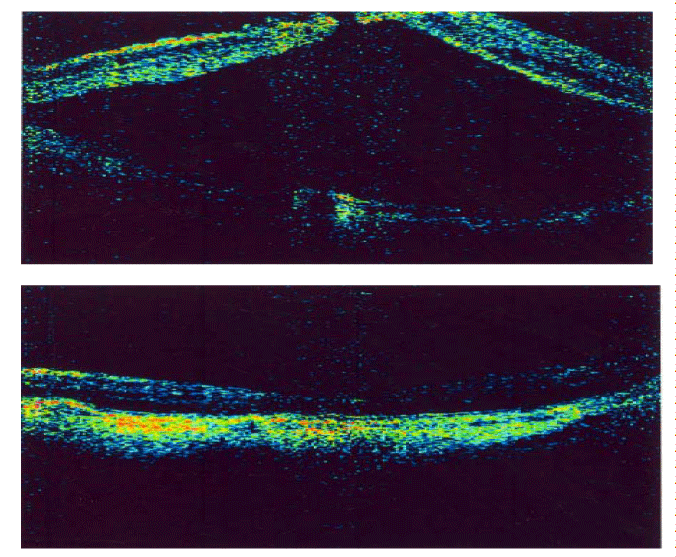

| Figure 2: Vitrectomy for myopic traction maculopathy (MTM) associated with retinal detachment. (Top) Preoperative image retinal detachment. Visual acuity was 20/800. (Bottom) six months after PPV MTM was reduced. Retinal detachment was resolved. Visual acuity was 20/200. |